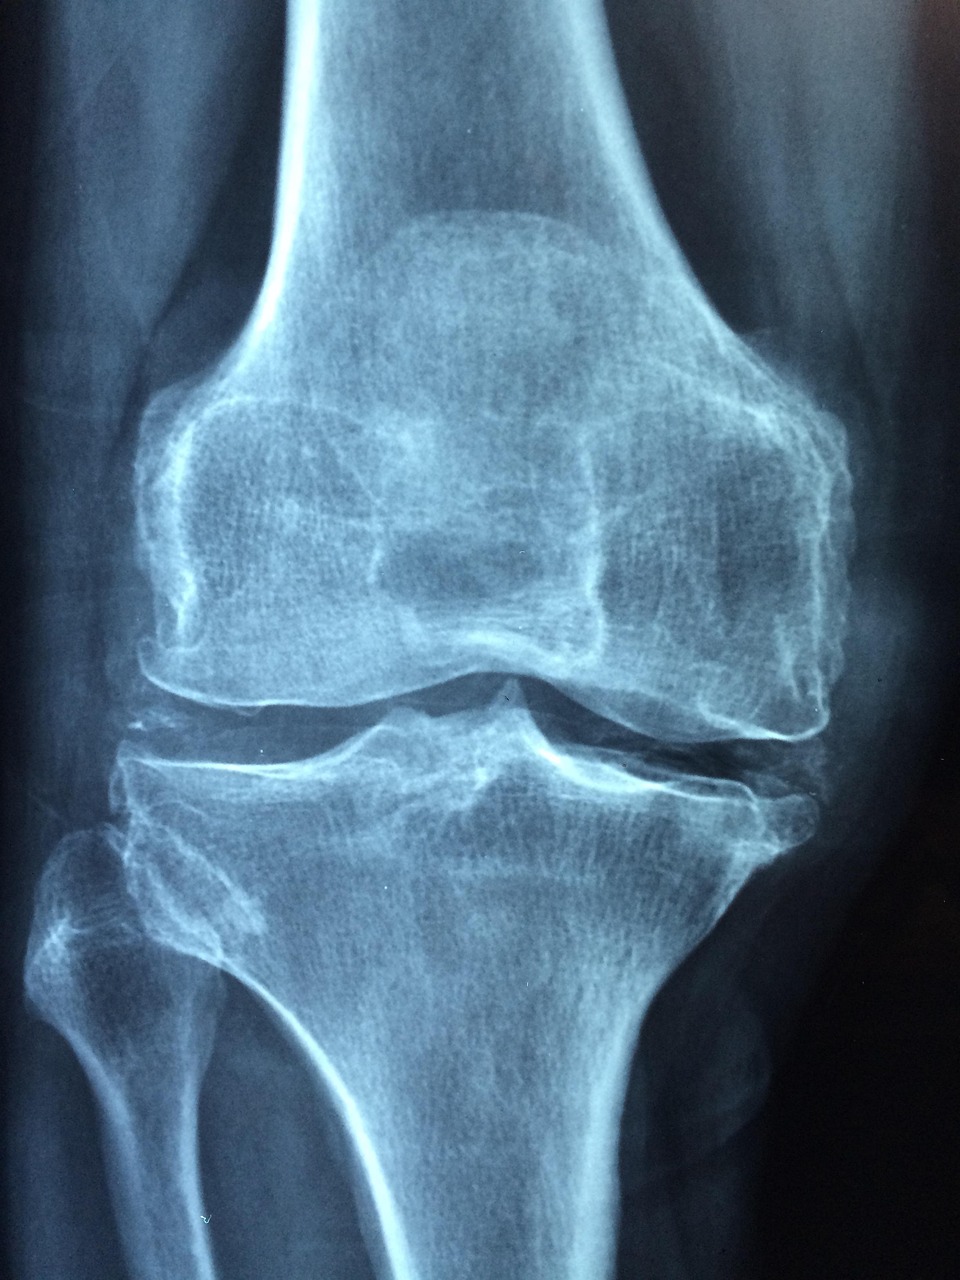

• Imaging studies such as X-rays or MRI